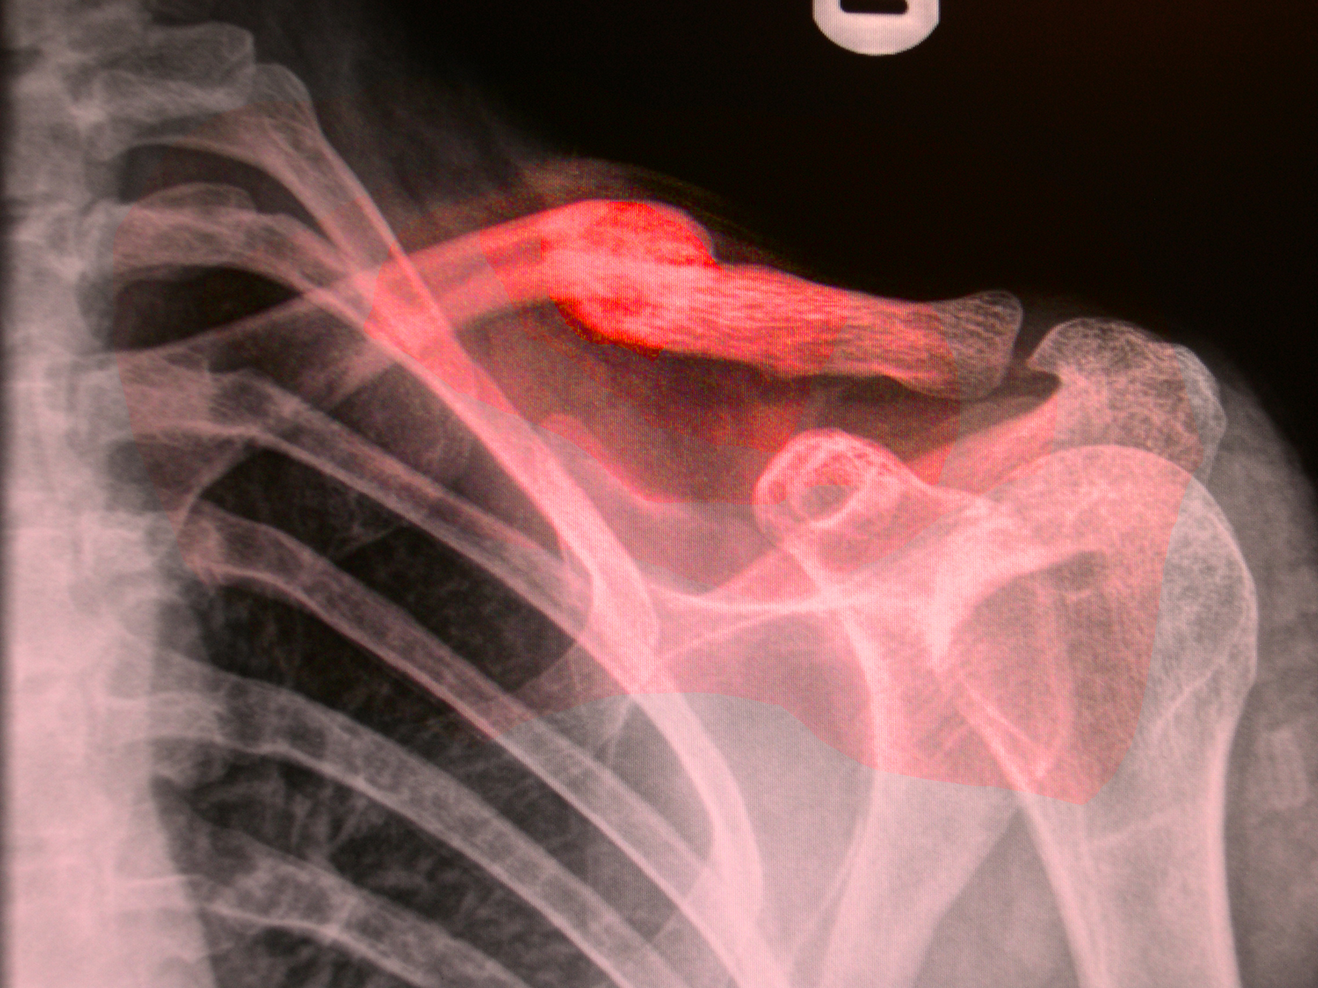

In 'Broken Arm' Henri Michaux observes, ‘A while ago, on the very spot where the accident took place, right after the fracture, when I didn’t know yet that my right elbow was broken, the spirit of my body had silently, secretly deserted it’ (1994: 244). Oliver Sacks describes his broken leg as a ‘phantom’ and ‘a corpse’s leg’ (1990: 88) and that, ‘...it was, in effect, mortified: it was neutrally, functionally and existentially dead’ (1990: 83). Ann Oakley based a book on the experience of breaking her arm and notes that, ‘It’s a shocking to experience part of one’s body as lifeless flesh when one ‘knows’ it isn’t’ (2007: 32). It seems that the lack of functioning and wasting away of a limb could provoke the same sense of abjection as a corpse. Sacks notes that his leg is, ‘...no longer a part of my ‘inner image’ of myself – having been erased from my body image, and also my ego, by some pathology of the most serious and inexplicable kind (1990: 81).

Broken bones, therefore, can present two elements that encourage us to take risks and move beyond everyday routines and restrictions. The first is in wanting to break free from the restricting feelings of being in plaster or having limited in. The second is that alienation to the broken limb moves us to face a state of uncertainty by bringing it forcefully into our awareness.

Chapter 3 of Oliver Sacks’s A leg to stand on explores the state of limbo he experienced for twelve days after he broke his leg. Sack’s suggests the state of limbo is a result of an interruption to order or ‘a rift in reality’ and equates this with the experience with the abyss.